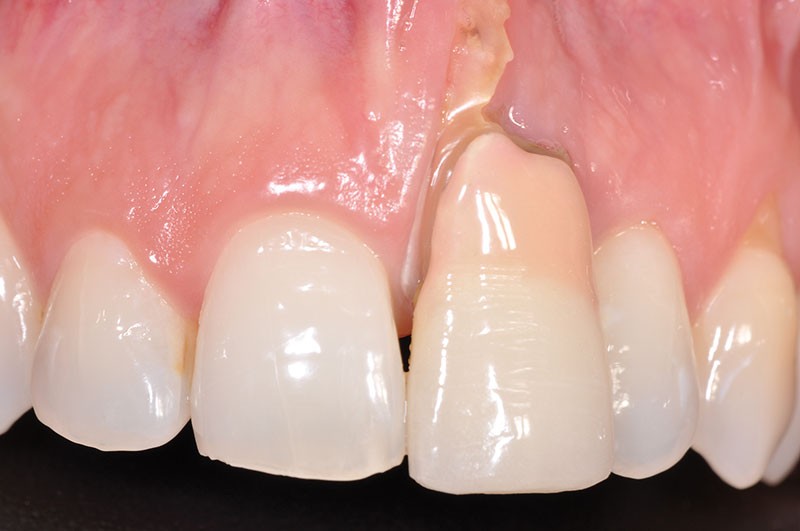

L’examen clinique montre que l’incisive centrale maxillaire gauche (21) est en exfoliation vestibulaire, elle présente une mobilité 2 de sa portion coronaire et interfère dans sa fonction (fig. 1, 2).

On objective, dans la partie la plus apicale du vestibule, la présence d’une zone infectieuse (abcès parodontal) causée, entre autres, par la forte résorption externe de la racine (fig. 3).